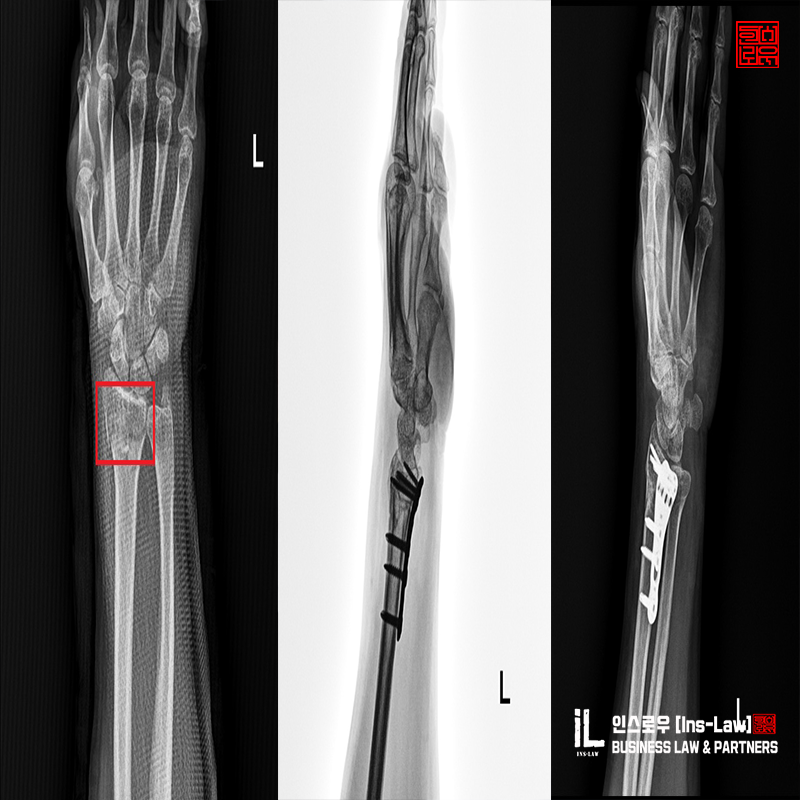

¼Õ¸ñ°ñÀýÀÇ »ç°íÀ¯ÇüÀº ´ëºÎºÐ ³ôÀº °÷¿¡¼ ¶³¾îÁú¶§ ¹Ý»çÀûÀ¸·Î ¸öÀ» ÁöÅÊÇϱâ À§ÇÑ ¹Ý»çÀûÀÎ ¹æ¹ýÀ¸·Î üÁßÀ» À̱âÁö ¸øÇÏ°í ¼Õ¸ñÀÌ °ñÀýµÇ´Â »ç·Ê°¡ °¡Àå ÈçÇÏ°Ô ÀϾ´Â °ñÀý»ç°íÁß¿¡ ÇϳªÀÔ´Ï´Ù. ¼Õ¸ñ¿¡¼ ¹ß²ÞÄ¡±îÁöÀÇ »À´Â ¿ä°ñ°ú ô°ñ °¢ 2°³ÀÇ »À°¡ À§Ä¡Çϰí ÀÖ½À´Ï´Ù.±ä Àå°ñÀ» ¿ä°ñÀ̶ó°í ÇÏ¸ç ¹Ý´ëÃø »À°¡ ô°ñÀÔ´Ï´Ù. ¿ä°ñÀ©À§ºÎ °ñÀýÀº ½ÉÀå¿¡¼ ¸Õ ÂÊÀ» ¿øÀ§ºÎ·ÎÇÏ¸ç °ñÀýºÎÀ§°¡ ¿ä°ñÀ̱⿡ ¿ä°ñ¿øÀ§ºÎ °ñÀýÀ̶ó°í ÇÕ´Ï´Ù. ¿ä°ñ°ú ô°ñÀÇ ±â´ÉÀº ÆÈ¿¡ ±¼½Å¿îµ¿°ú ȸÀü¿îµ¿À» ÀÌ·ç±â¿¡ °ñÀýÀÌÈÄ ÀçȰġ·á°¡ »ó´çÈ÷ Áß¿äÇÏ´Ù°í ÇÒ ¼ö ÀÖ½À´Ï´Ù.

¨ç ¿ìÃø Àü¿ÏºÎ Á¤Áß½Å°æ ¹× Ã¶°ñ½Å°æ ÆÄ¿

¨è ¿ìÃø ³»Ãø ¹× ¿ÜÃø Àú¿ÏºÎ Ç¥Àç½Å°æ ÆÄ¿

¨é ¿ìÃø Àü¿ÏºÎ ¿ä°ñ ¹× ö°ñ µ¿¸ÆÆÄ¿

¨ê ¿ìÃø Àü¿ÏºÎ ¼öÁö ¹× ¼ö±Ù ±¼°Ç ÆÄ¿